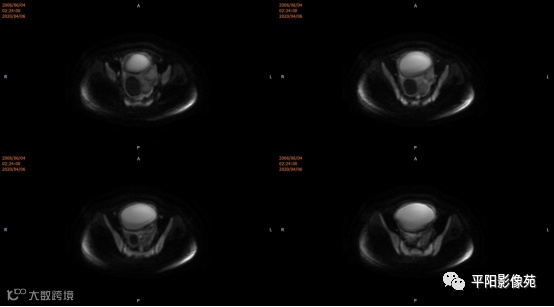

患者,女,13岁

主诉: 下腹部胀痛2+月,加重1天

现病史: 患者月经未来潮,2+月前无明显诱因感下腹部憋胀,间断胀痛,可忍耐,伴排便困难,自认为便秘引起腹胀,未在意。近1+月腹胀、胀痛次数增加,觉下腹部逐渐增大,小便正常。

您的诊断?

子宫10cm×12cm大小,饱满,呈紫红色,子宫下段增粗膨大呈柱状,右侧卵巢可见一约18*15cm大小的肿物,表面呈紫红色,输卵管明显增粗膨大,伞端及卵巢粘连包裹于子宫后壁及侧盆壁,左侧卵巢可见一约8*7cm大小的囊肿,左侧输卵管增粗膨大伞端包裹粘连于子宫后壁及侧盆壁,直肠粘膜粘连于子宫后壁。部分大网膜粘连于子宫及卵巢表面。 注射器针头刺入子宫肌层至宫腔,抽取出大量暗红色血液,宫腔内积血,子宫缩小,子宫下段膨大,不排除生殖道畸形,双侧卵巢巧克力囊肿可能,钝性分离粘连,针头刺入右侧卵巢囊腔,吸出咖色液体约800ml,娩出右侧卵巢,切开右侧卵巢囊肿表面组织达囊壁,钝性剥离囊肿,剥离过程中可见大量黑褐色液体流出,3-0可吸收线缝合囊腔止血使卵巢成形,大小约5*6cm,同法处理左侧,使左卵巢成形,分离双侧输卵管粘连,暴露伞端,行宫腔穿刺可抽取出大量暗红色血液,考虑生殖道畸形,需改阴式手术探查,破坏处女膜,术中向患者家属交待病情,需改阴式手术破坏处女膜,患者家属表示理解,同意改阴式探查并签字。 患者取膀胱截石位,常规消毒铺巾,见外阴外观发育正常,分开小阴唇,见尿道口下方可见处女膜环,剪开处女膜环,可见阴道壁约1cm,前为盲端,分开处女膜后,于尿道下方阴道口位置,将1:10000的肾上腺素注入阴道直肠间隙,在尿道口下方阴道壁痕迹处横切约2.5cm,钝性分离,可及一囊肿,表面淡紫色,20ml注射器经此处穿刺,抽出暗褐色积血,用注射器向阴道积血方向穿刺,抽出褐色积血,探查囊腔与宫腔相通,未见明显宫颈组织,上段未见阴道粘膜,考虑宫颈缺如及生殖道畸形,清理宫腔积血,将子宫下段最低端缝合于约1cm的阴道粘膜上,形成宫颈形状,宫腔放置一根引流管,查无出血。

宫颈缺如、阴道闭锁

4.MRI检查 对软组织分辨率好,能够清晰区分子宫及阴道,对子宫内膜、结合带、肌层可清晰分辨;能明确子宫、宫颈、阴道结构异常的部位、范围、性质等。宫腔内经血潴留时,宫腔内见短T1长T2信号。